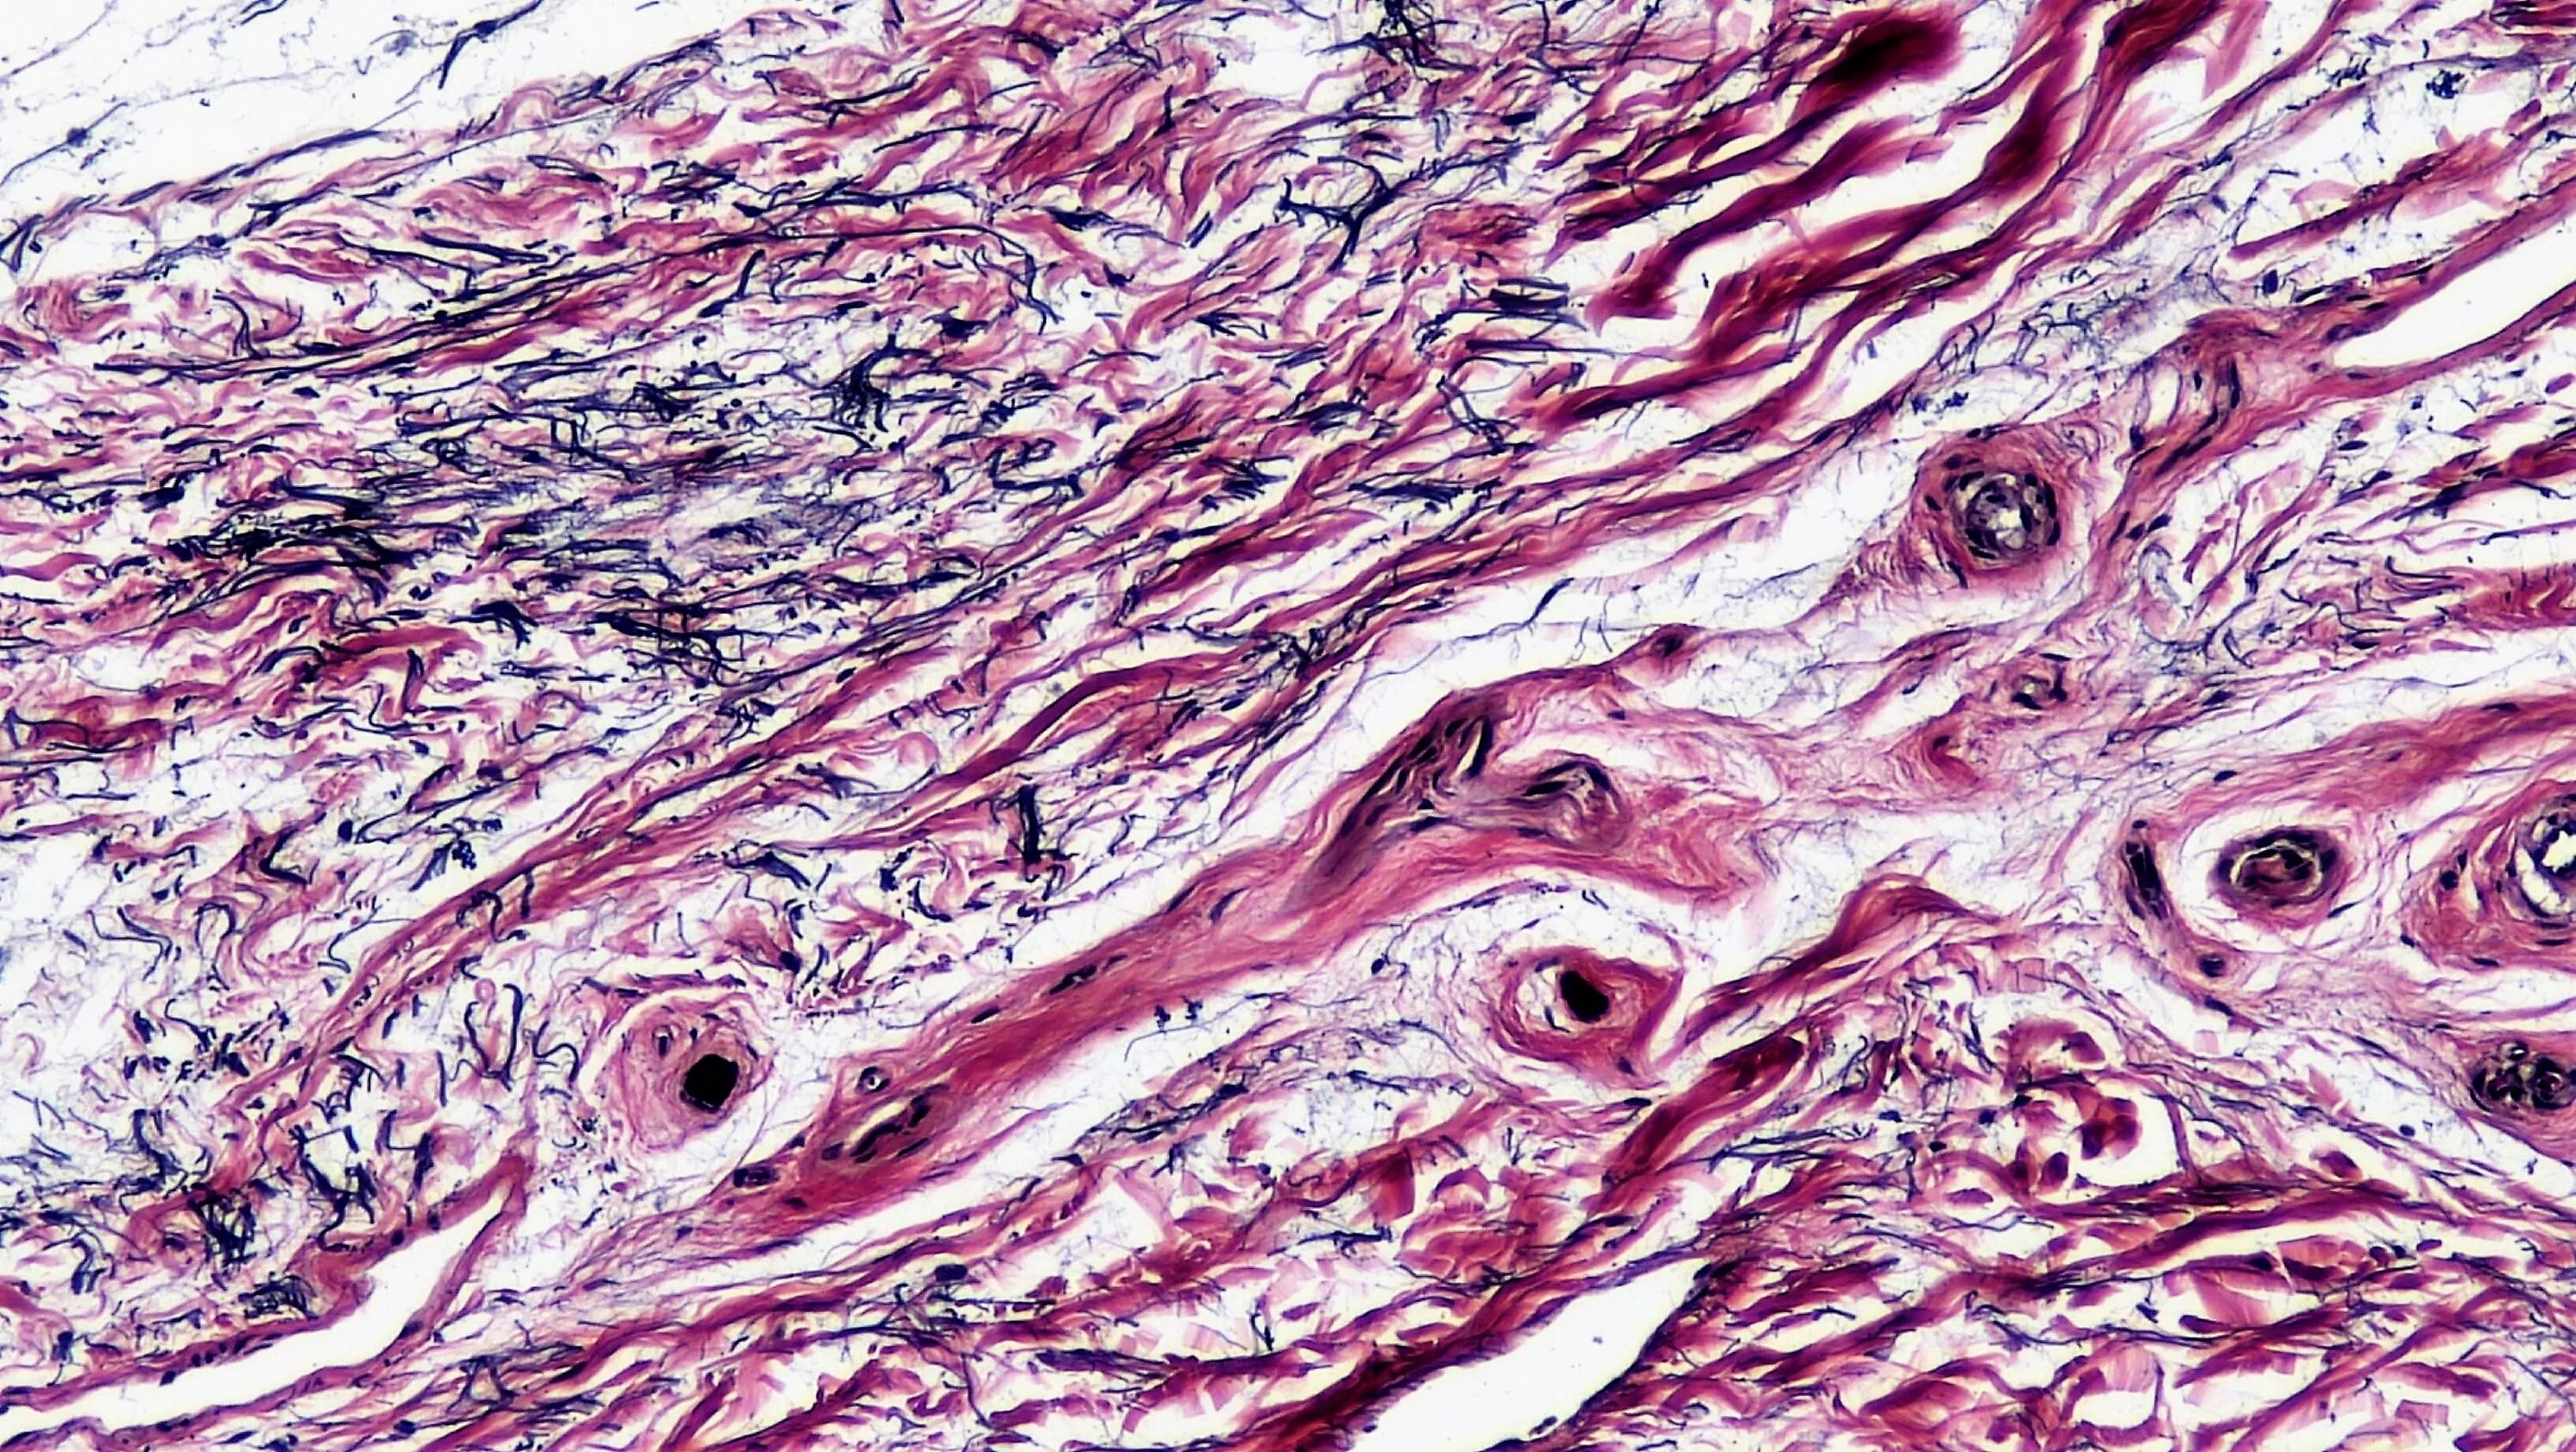

Фото тканей человека